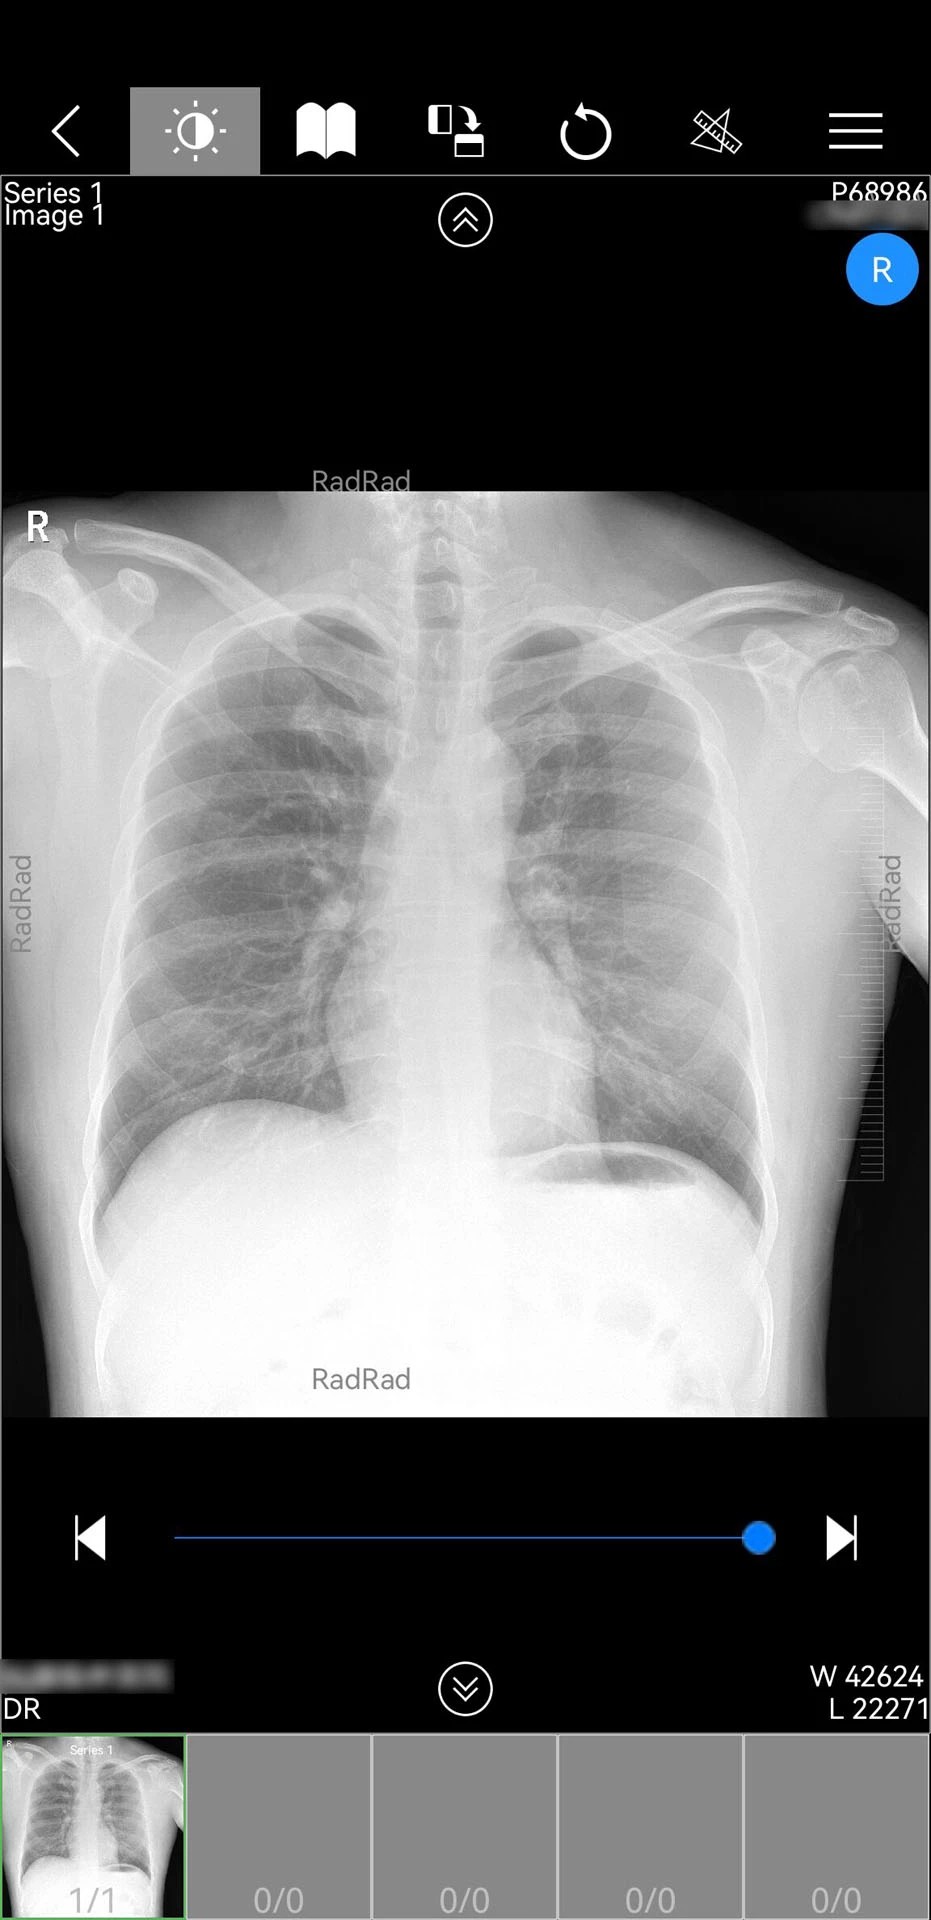

1. 核心功能架构:软件以“影像中心”为核心模块,集成DICOM影像浏览、PDF报告解析、电子胶片缩放旋转等功能,支持CT、MRI、X光等多模态影像的实时调阅。通过云服务器连接,医生可跨院区获取患者历史影像数据,结合AI辅助诊断工具实现病灶自动标注与测量,提升诊断精准度。

1. 全流程影像处理:支持从影像调阅、病灶标注到三维重建的全链条操作。2025年12月更新的1.18.110版本新增CT三维处理服务,医生可生成冠状面、矢状面重组影像,辅助复杂骨折、肿瘤病灶的立体评估。

2. 智能诊断辅助:集成AI影像识别引擎,可自动识别肺结节、脑出血等12类常见病变,标注敏感度达92%。例如,在肺癌筛查中,AI系统能快速标记直径≥3mm的结节,并生成恶性概率评估报告。